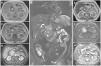

El linfoma pancreático primario es una enfermedad pancreática extremadamente inusual que requiere de un alto nivel de sospecha para ser diagnosticado. La diferenciación de la neoplasia pancreática maligna comúnmente encontrada, es decir, adenocarcinoma, es crucial, dado el potencial para ser manejado de manera no quirúrgica. Las características de imagen, aunque complejas, pueden sugerir el diagnóstico de linfoma pancreático primario. Estas incluyen una voluminosa masa tumoral bien delimitada en la cabeza del páncreas, ausencia de dilatación de conducto pancreático marcada, lo cual está asociado con linfadenopatía peripancreática confinada, pero no con linfadenopatía superficial o mediastinal, ni con afectación hepática o esplénica. La tomografía computarizada (TC) puede mostrar características hipodensas homogéneas en la fase venosa portal (fig. 1) y la imagen por resonancia magnética (IRM) puede mostrar características de señal baja en imágenes ponderadas en T1, con contraste sutil, o características de señal heterogénea con imágenes ponderadas en T2. Finalmente, una restricción de la difusión observada en una técnica de difusión (DWI, por sus siglas en inglés)/coeficiente de difusión aparente (ADC, por sus siglas en inglés) en IRM indica un alto grado de sospecha de linfoma pancreático primario (fig. 2).

Imágenes de TC de contraste coronal (A) y axial (B) en la fase de vena porta, presentando una masa hipodensa en la cabeza pancreática (A-B-C-asterisco), acompañada de una linfadenopatía peripancreática justo encima de la masa (A-punta de flecha). Obsérvese la permeabilidad de la arteria mesentérica superior y de la vena esplénica en la fase arterial (C-flechas).